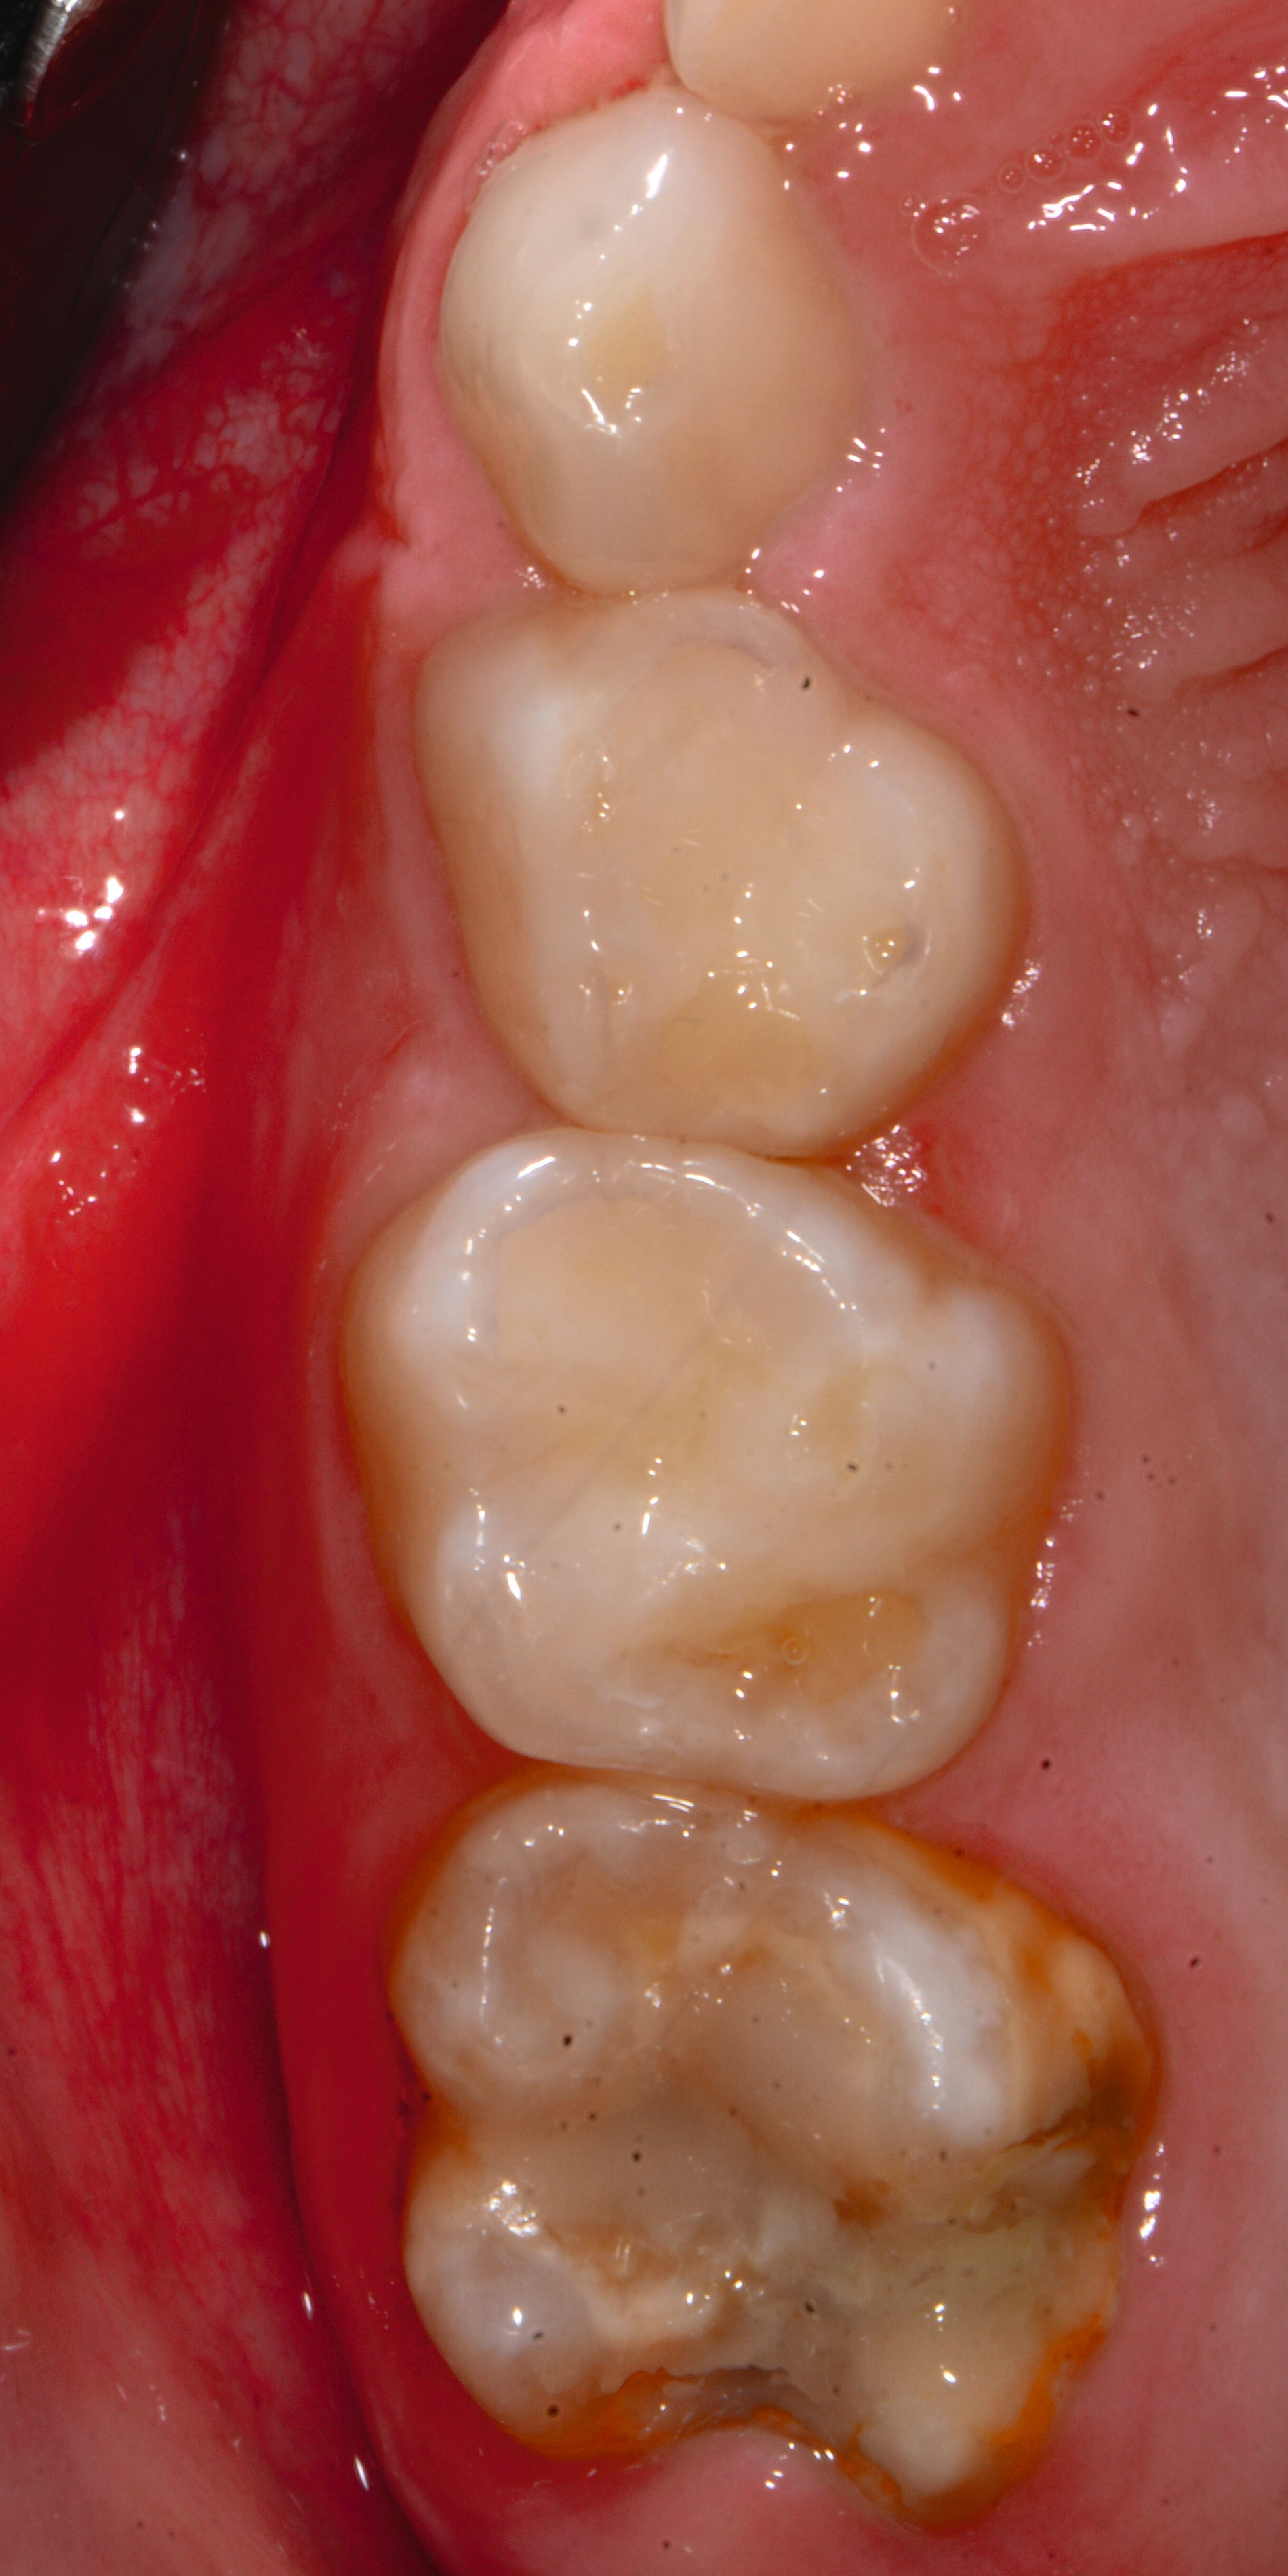

An umfangreich hypomineralisierten Zähnen können Schmelzeinbrüche (engl.: „enamel breakdown“ oder „enamel desintegration“, Abbildung 5) auftreten [Lygidakis et al., 2010; 2022]. Da diese oftmals die Folge einer fehlenden Belastungsfähigkeit des Zahnschmelzes sind und erst nach der Einstellung der Zähne in die Okklusion auftreten, werden sie auch als posteruptive Schmelzeinbrüche bezeichnet. Sie sind häufig im Bereich der Kauflächen beziehungsweise Höcker der Molaren zu finden, führen zur Dentinexposition und damit einhergehend zu ausgeprägten Hypersensitiven insbesondere bei Kindern, deren Zähne gerade erst durchgebrochen sind [Linner et al., 2021].

Bei post- beziehungsweise präeruptiven Oberflächendefekten ergibt sich in einigen Fällen die Indikation zur Restauration dieser MIH-Zähne. Unter Verweis auf die Lokalisation von MIH-bedingten Hypomineralisationen außerhalb der typischen Kariesprädilektionsstellen – zum Beispiel okklusale Fissuren und Grübchen oder Approximalflächen – werden diese als „atypische Restaurationen“ (engl.: „atypical restoration“, Abbildung 6) klassifiziert. Als ein weiteres Erkennungsmerkmal gilt die Präsenz von Hypomineralisationen im Bereich der Restaurationsränder. MIH- und kariesbedingte Restaurationen können und sollten sicher voneinander abgegrenzt werden.